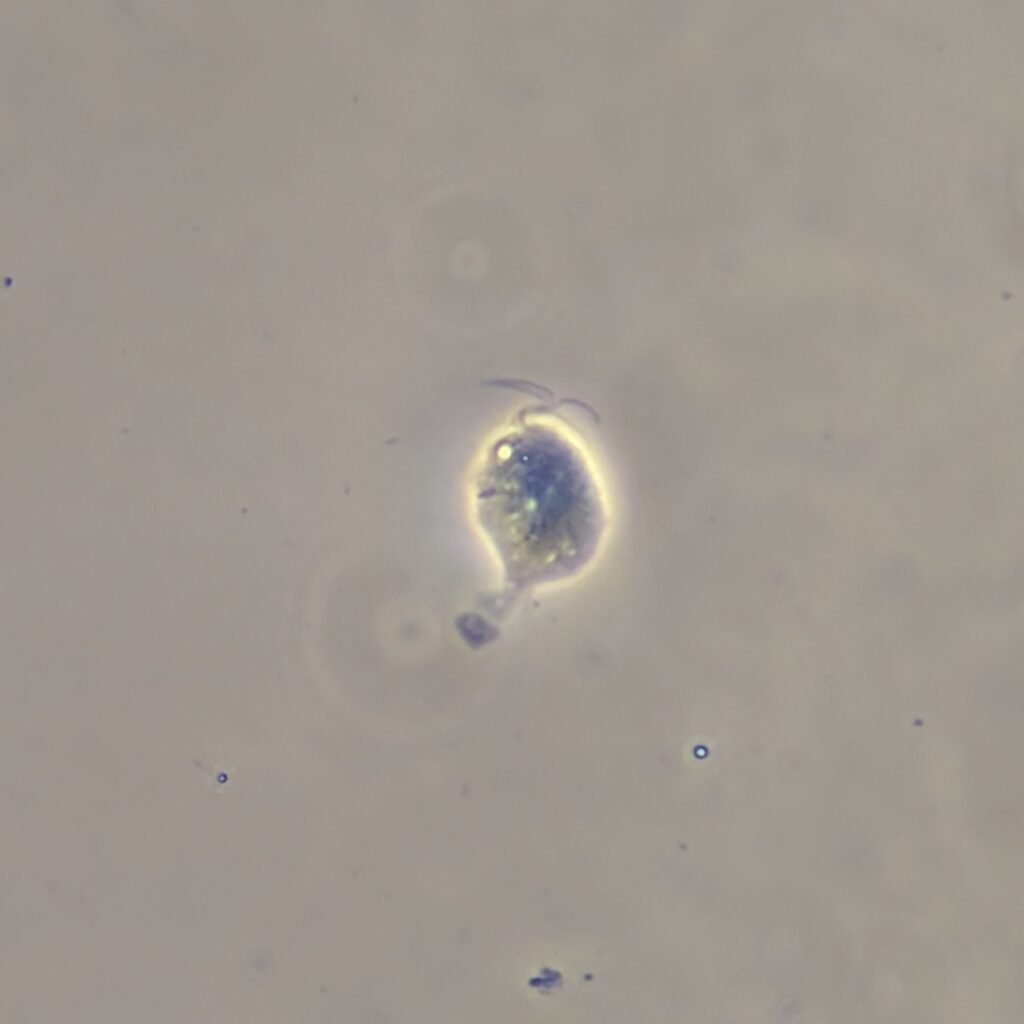

Trichomonas are pear-shaped and have four flagella. Motility is usually necessary for identification.

Trichomonas can look like a white blood cell when non-motile which is why motility is usually necessary to positively identify by microscopy.

Gallery